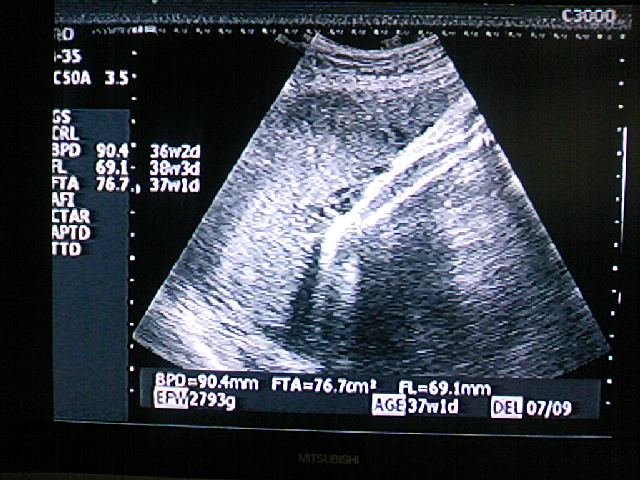

37w1d(予定日7月9日)

推定体重:先週(6/12)2747g→今回(6/19)2793g

BPD(児頭大横径・・赤ちゃんの頭の直径)90.4mm 36w2d

FL(大腿骨長・・ふとももの骨の長さ) 68.8mm 38w3d

FTA(胎児胸郭断面積) 76.7mm 37w1d

前回2800と書きましたが(おおざっぱに)実際には上の通り

2747g→2793gに若干増えてました。